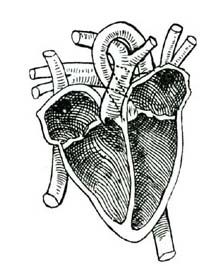

[Pg 50]4. The Heart Chambers.—The heart has four chambers, two upper and two lower chambers. The blood is received into the upper chambers, and is then passed down into the lower chambers. From the lower chambers it is sent out to various parts of the body.

5. The Blood-Vessels.—The tubes through which the blood is carried are called blood-vessels. There are three kinds of blood-vessels. One set carry the blood away from the heart, and are called arteries (ar'-te-ries). Another set return the blood to the heart, and are called veins. The arteries and veins are connected at the ends farthest from the heart by many very small vessels. These minute, hairlike vessels are called capillaries (cap'-il-la-ries).

6. The Arteries.—An artery leads out from the lower chamber of each side of the heart. The one from the right side of the heart carries the blood only to the lungs. The one from the left side of the heart carries blood to every part of the body. It is the largest [Pg 51]artery in the body, and is called the aorta. Soon after it leaves the heart the aorta begins to send out branches to various organs. These divide in the tissues again and again until they become so small that only one corpuscle can pass through at a time, as shown in the colored plate. (Frontispiece.)

7. The Veins.—These very small vessels now begin to unite and form larger ones, the veins. The small veins join to form larger ones, until finally all are gathered into two large veins which empty into the upper chamber of the right side of the heart. The veins which carry blood from the lungs to the heart empty into the upper chamber of the left side of the heart.

8. What is Done in the Blood-Vessels.—While the blood is passing through the small blood-vessels in the various parts of the body, each part takes out just what it needs to build up its own tissues. At the same time, the tissues give in exchange their worn-out or waste matters. The red blood corpuscles in the capillaries give up their oxygen, and the blood receives in its stead a poisonous substance called carbonic-acid gas.

9. Red and Blue Blood.—While in the arteries the blood is of a bright red color; but while it is passing through the capillaries the color [Pg 52]changes to a bluish red or purple color. The red blood is called arterial blood, because it is found in the arteries. The purple blood is called venous blood, because it is found in the veins. The loss of oxygen in the corpuscles causes the change of color.

10. Change of Blood in the Lungs.—Exactly the opposite change occurs in the blood when it passes through the lungs. The blood which has been gathered up from the various parts of the body is dark, impure blood. In the lungs this dark blood is spread out in very minute capillaries and exposed to the air. While passing through the capillaries of the lungs, the blood gives up some of its impurities in exchange for oxygen from the air. The red corpuscles absorb the oxygen and the color of the blood changes from dark purple to bright red again. The purified blood is then carried back to the upper chamber of the left side of the heart through four large veins. The blood is now ready to begin another journey around the body.